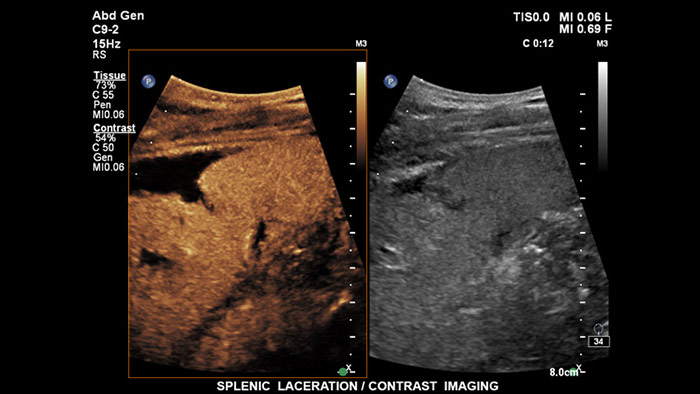

Ultrasonidos con contraste

Los agentes de contraste para ultrasonidos pueden transformar el papel que desempeñan los ultrasonidos hepáticos, pues permiten que el usuario estudie los patrones de mejora de las lesiones hepáticas sospechosas en tiempo real, lo que ofrece la posibilidad de realizar diagnósticos más fiables y rápidos. Con EPIQ de Philips, los CEUS se integran a la perfección en el flujo de trabajo normal y proporcionan un nivel de detalle excepcional en exploraciones de la fase arterial, portal y tardía. Además, EPIQ ofrece el mayor nivel de fiabilidad posible para la detección y caracterización de lesiones, incluso en las exploraciones más difíciles; esto es posible gracias a tecnologías avanzadas al alcance de su mano, entre las que cabe mencionar las siguientes: pantalla MaxVue FHD, transductor PureWave C9-2, imágenes de fusión y cuantificación Q-App.

Ultrasonidos con contraste

Los agentes de contraste para ultrasonidos pueden transformar el papel que desempeñan los ultrasonidos, pues permiten que los profesionales sanitarios estudien los patrones de mejora de las lesiones hepáticas en tiempo real, lo que ofrece la posibilidad de realizar diagnósticos más definitivos y rápidos. Con los ultrasonidos de Philips, los ultrasonidos con contraste se integran a la perfección en el flujo de trabajo normal y ofrecen un nivel de detalle excepcional.